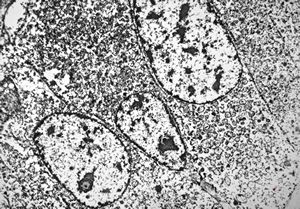

F, 71y. | carcinoid … metastasis to lymphonode